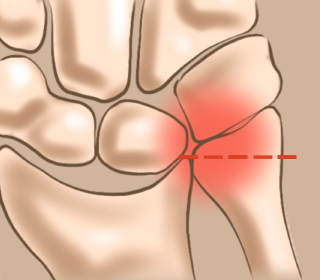

척골 충돌 증후군

손목관절에는 두 개의 큰 뼈인 요골과 척골이 있는데 손목의 과도한 사용이나 외상, 퇴행성 변화 등으로 요골이 단축되고 척골이 상대적으로 길어져 척골과 수근골이 충돌하면서 통증이 나타나는 질환입니다.

척골이 길어진 모습